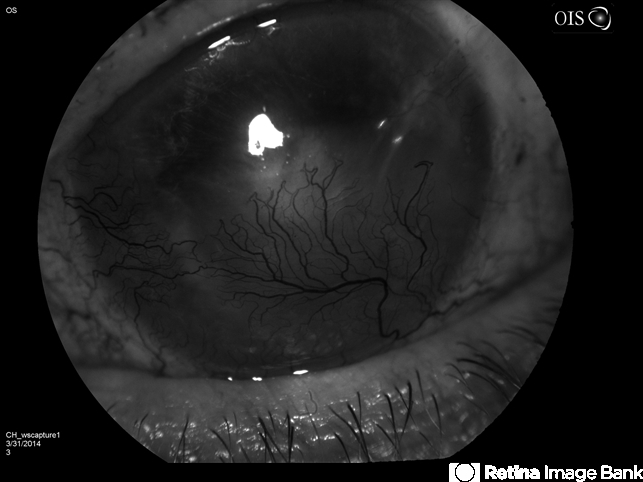

Looks like neovascularization of the cornea in a stromal scar. Possible HSV or HZO

- neovascularization (NV), cornea

- Neovascularization of the Cornea